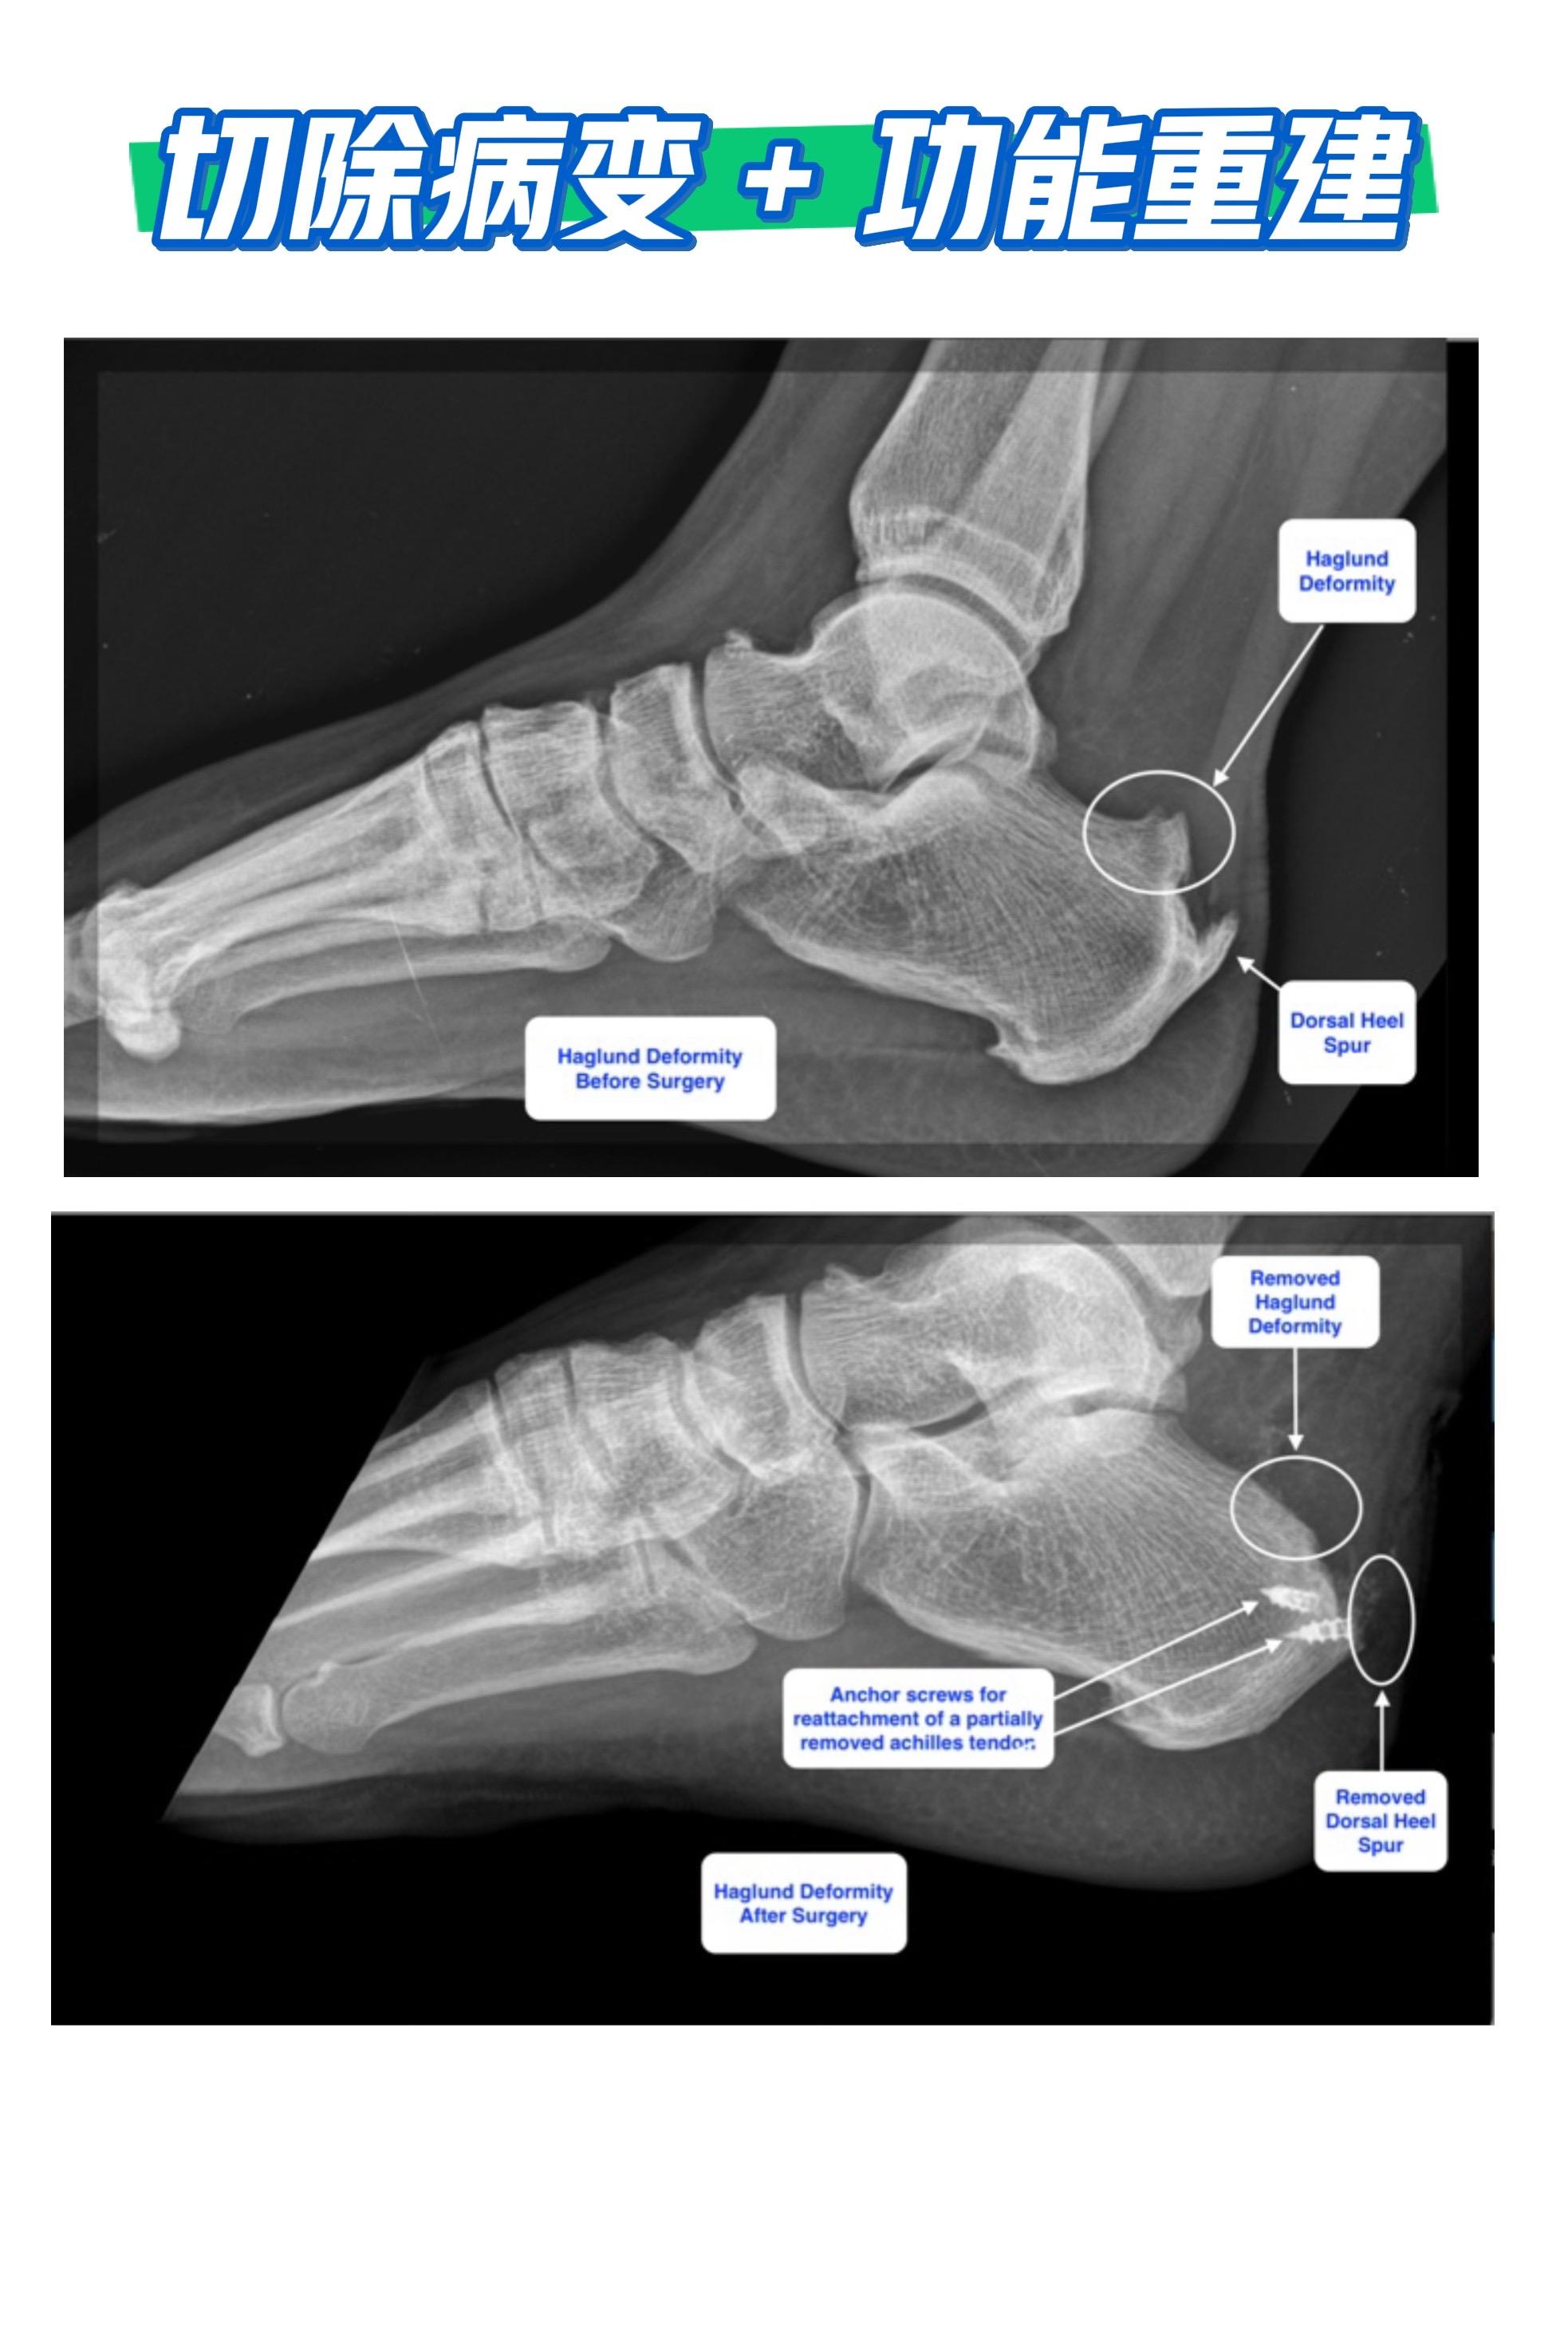

Haglund畸形。切除病变 + 功能重建。